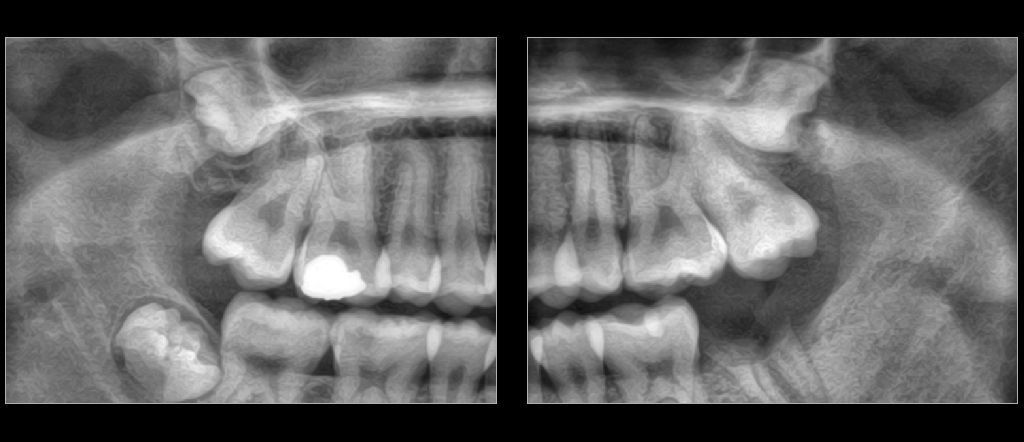

Uno de nuestros principales servicios es la adquisición de imágenes dentales 2D y 3D, fundamentales para un diagnóstico preciso y una planificación adecuada de tratamientos dentales.

Contamos con tecnología avanzada que nos permite obtener imágenes claras y detalladas de la boca y los tejidos circundantes, lo que es crucial para evaluar la salud dental y detectar posibles problemas.